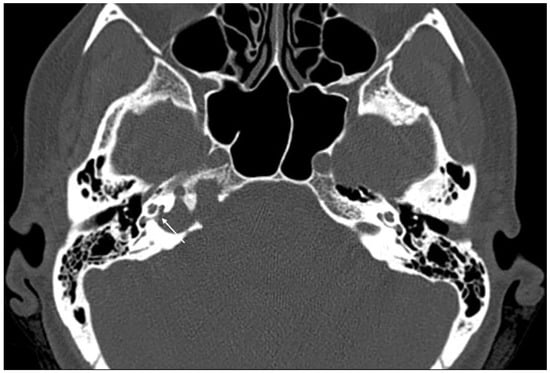

Imaging data from each patient were examined by an expert radiologist and an ENT specialist focusing attention not only on the location of the cyst, but also on the adjacent structures involved. Considering the available literature on symptoms and hypothesized regions of radiological involvement, we established a reproduceable pre-operative radiologic map to better correlate typical symptoms, such as headache, hearing loss, vestibular symptoms, tinnitus, otitis media, diplopia, and facial paresthesia, with PACG. The following regions were considered: (1) temporal lobe/posterior fossa compression (Figure 1); (2) Meckel’s cave compression (Figure 1); (3) Eustachian tube compression/erosion (Figure 2); (4) internal auditory canal erosion (Figure 3); (5) cochlear basal turn erosion (Figure 4); (6) Dorello canal involvement (Figure 5); (7) jugular tubercle erosion. The latter parameter was introduced to evaluate its possible correlation with an atypical clinical presentation, namely fainting. To standardize all these radiological examinations, the jugular tubercle was defined in axial sections as the bony convexity medial to the jugular foramen just above the hypoglossal canal; in coronal sections, it is the bony part directly above the hypoglossal canal (Figure 6).

Figure 4. Axial CT scan showing erosion of the right cochlear basal turn (white arrow) by a cholesterol granuloma.